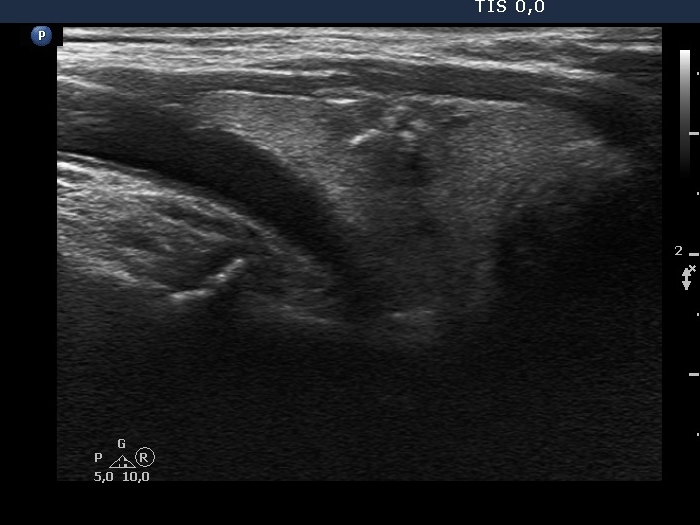

Lymph nodes - case 2050 (ultrasonographic picture 3)

Right lobe, another longitudinal scan.